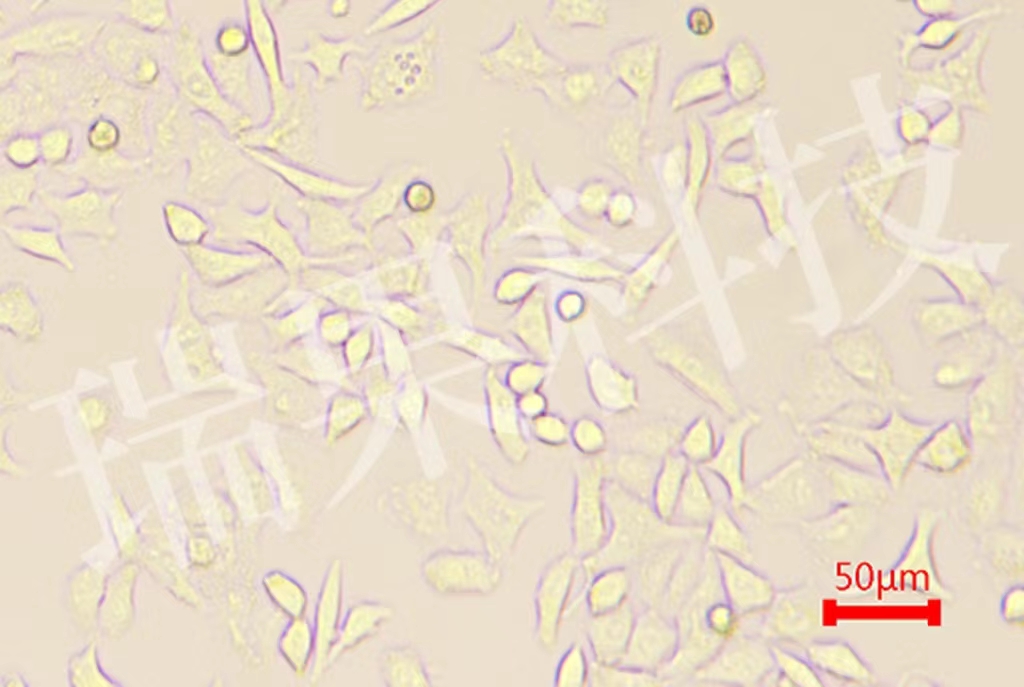

A549